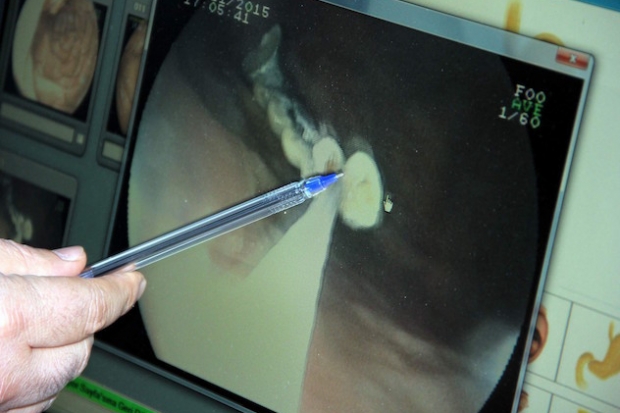

Gaziantep’te nohut dürümü yediği sırada 5 dişinin olmadığını fark eden 54 yaşındaki A.B., Dr. Ersin Aslan Devlet Hastanesinde muayene olduktan sonra kaybolan 5 dişi midesinden çıktı. Ameliyatı gerçekleştiren Gastroenteroloji Uzmanı Dr. Ahmet Yağbasan, “Cumartesi günüydü, bir tane diş yutma vakası olduğu söylendi. Öncellikle biz onu tam protez zannettik. Tam protez olsaydı. Biz onu çıkaramayabiliriz dedik. Daha sonra telefondan resmini gönderiler. Midede beş dişlik bir protez olduğunu gördük. Onu çıkarabiliriz diye düşündük. Normal filmde midede olduğu görünüyordu. Ama mideye baktığımızda dişleri göremedik. Dolayısıyla ilerlemiş olabileceğinin düşündük. Hastayla konuştuk nasıl olmuş diye, Antep nohut dürümü yerken dişinin eksik olduğunu hissetmiş. Bağırsak tıkanıklığına neden olabilecek bir protezdi. Yaklaşık 3 saat ameliyat sonrası dişleri çıkardık” şeklinde konuştu.